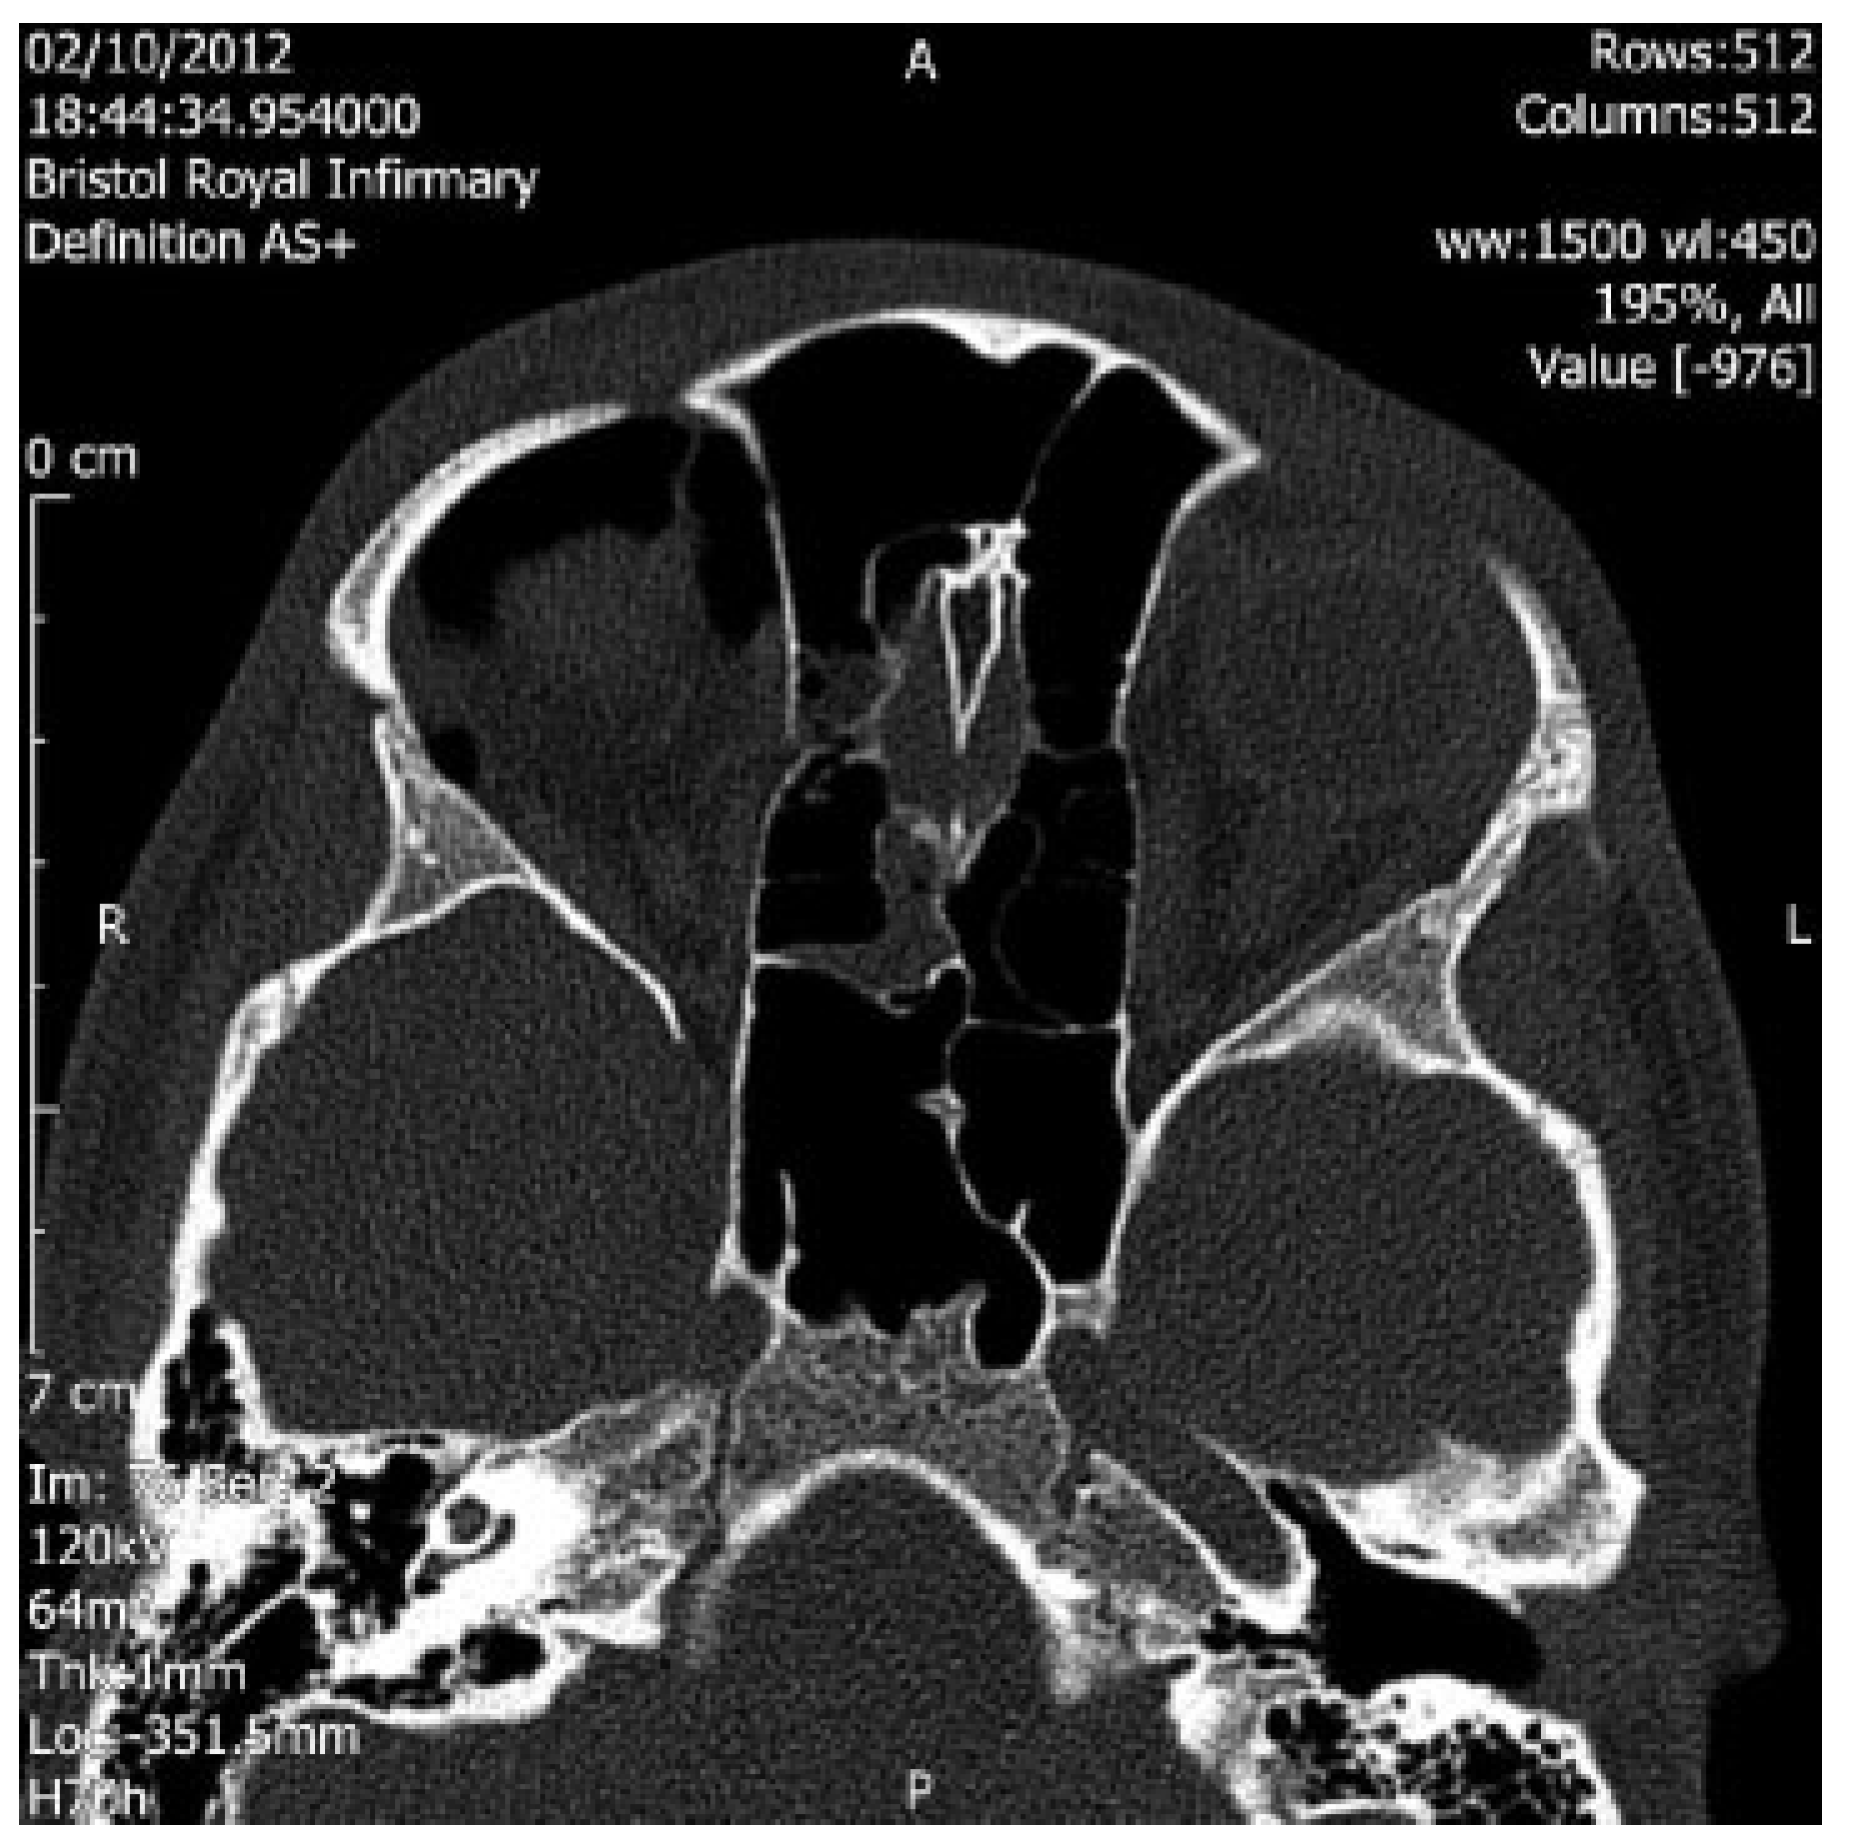

Medial Wall Fracture and Orbital Emphysema Mimicking Inferior Rectus Entrapment in a Child

:Case Report